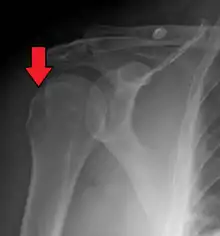

| Anterior shoulder dislocation on X-ray with a large Hill–Sachs lesion | |